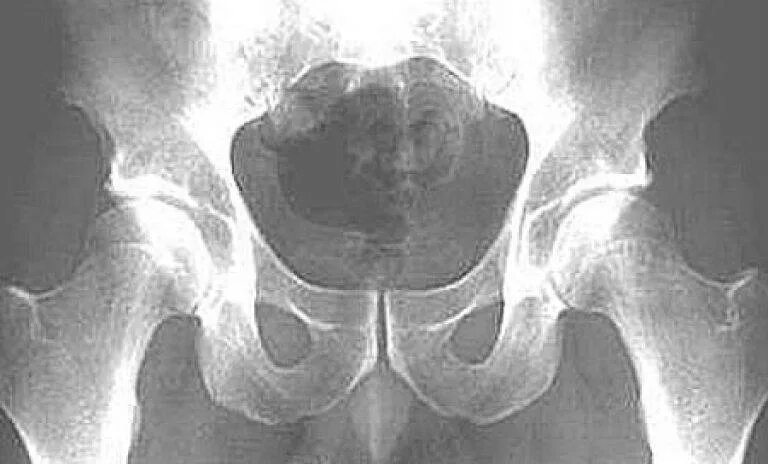

Симфизит при беременности 1 степень